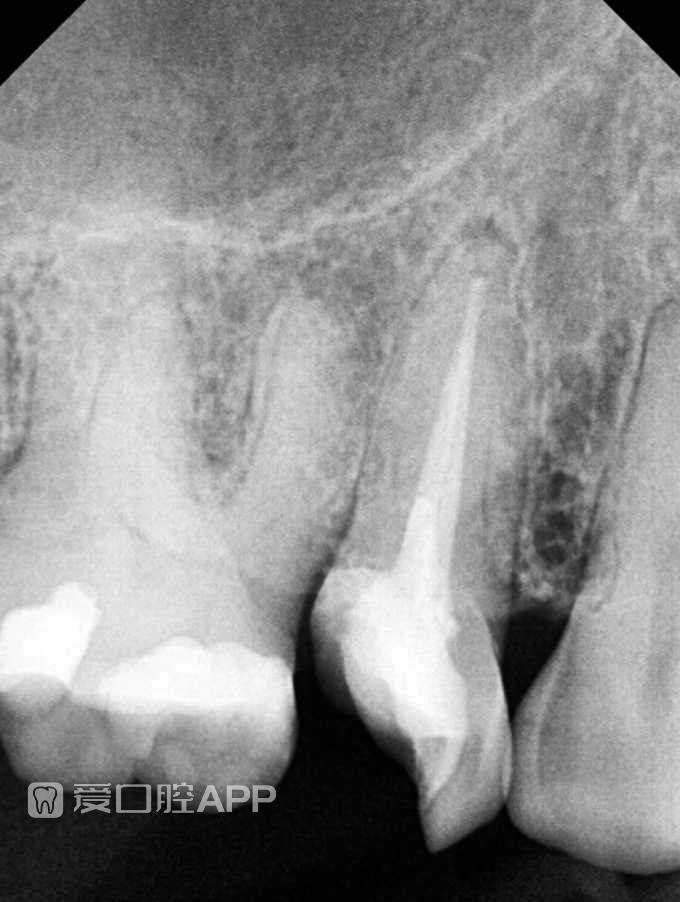

看个嵌体修复 —— 上颌第一前磨牙 附1年后随访

唯一遗憾就是有点欠充